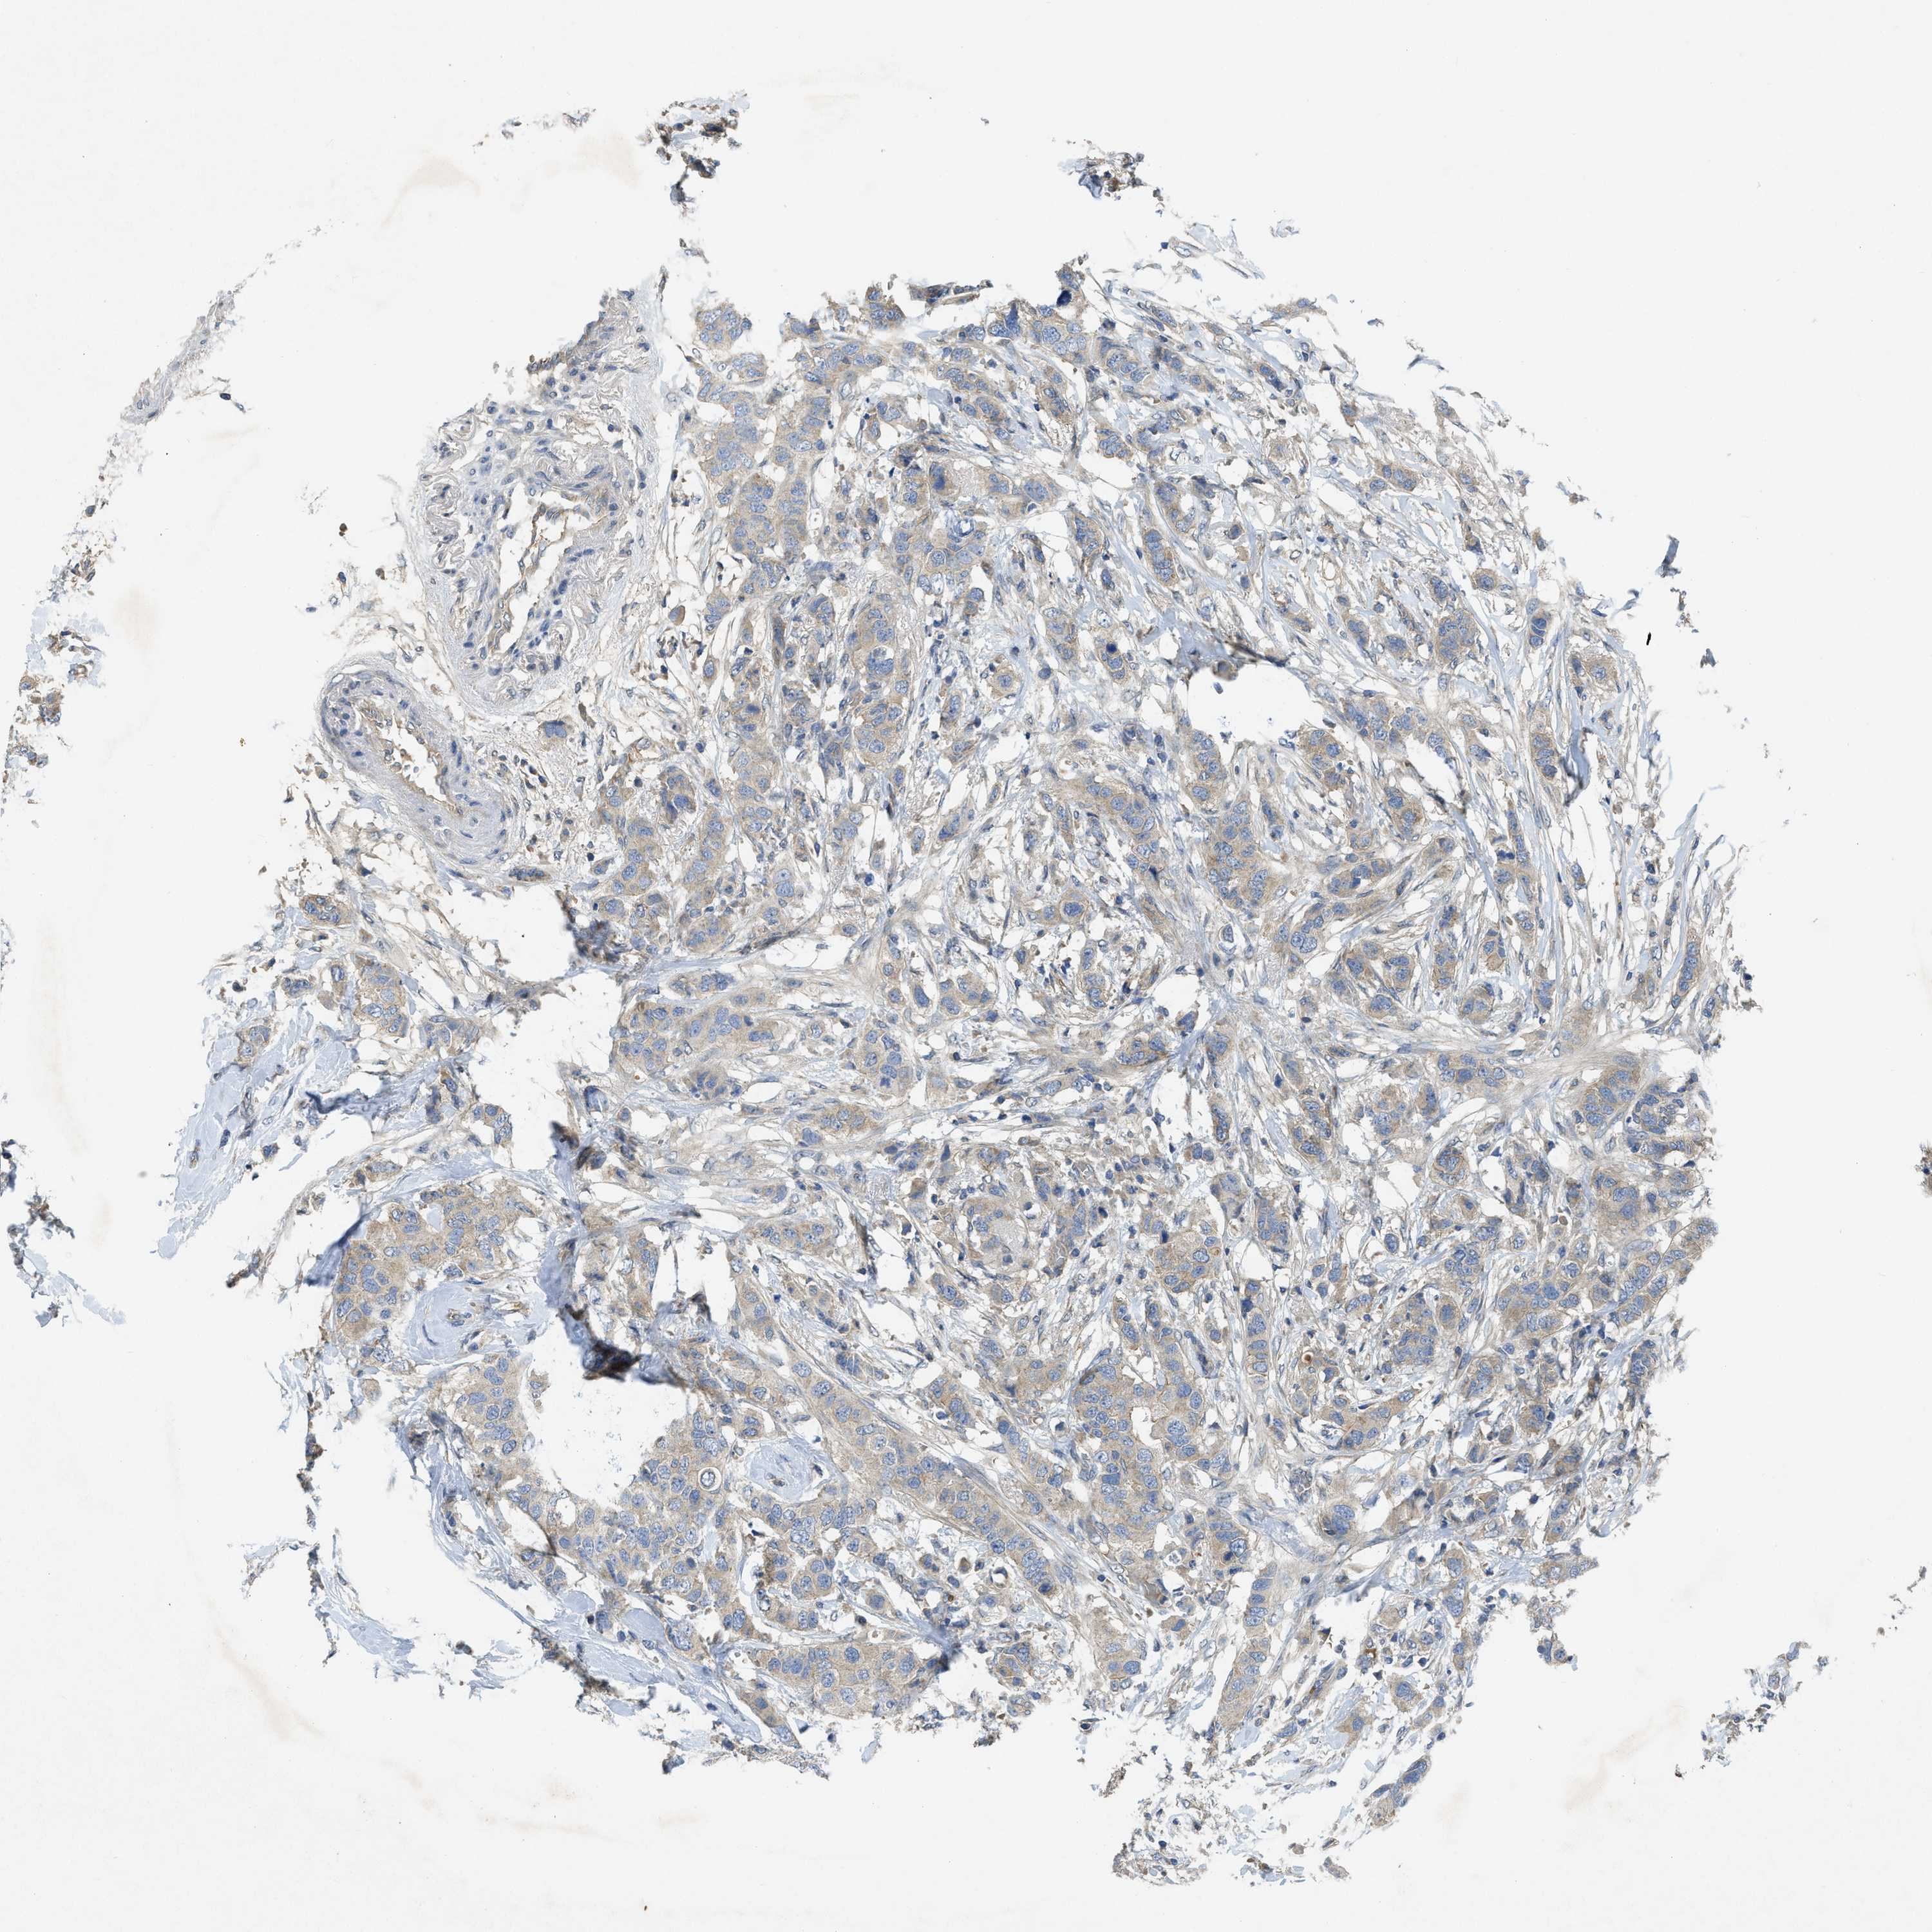

CANCER BREAST CANCER Show tissue menu

BRCA TCGA BRCA VALIDATION PROTEIN EXPRESSION